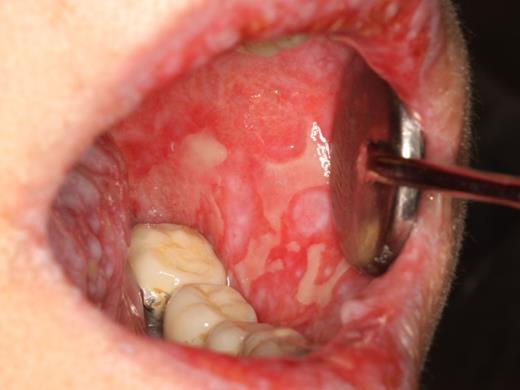

cGVHD of the buccal mucosa with extensive multifocal areas of ulceration interspersed with erythema and reticulation.